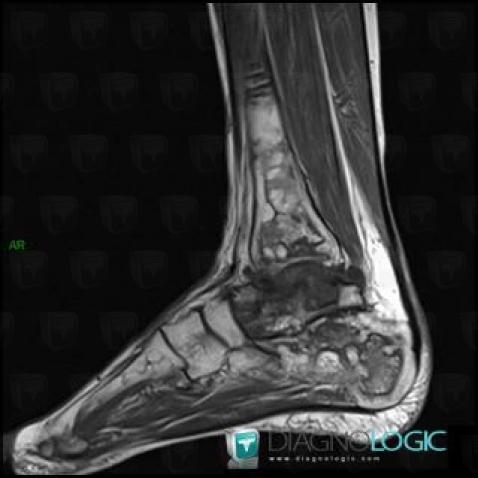

Avascular necrosis, Talus, MRI

Here is the specific information in the key image above:

- Diagnosis Avascular necrosis, Location(s) Talus, with gamuts T2 WI Hypointense bone lesion

Avascular necrosis, Tibia - Distal part, X rays

- Diagnosis Avascular necrosis, Location(s) Tibia - Distal part, with gamuts Well-defined osteolysis